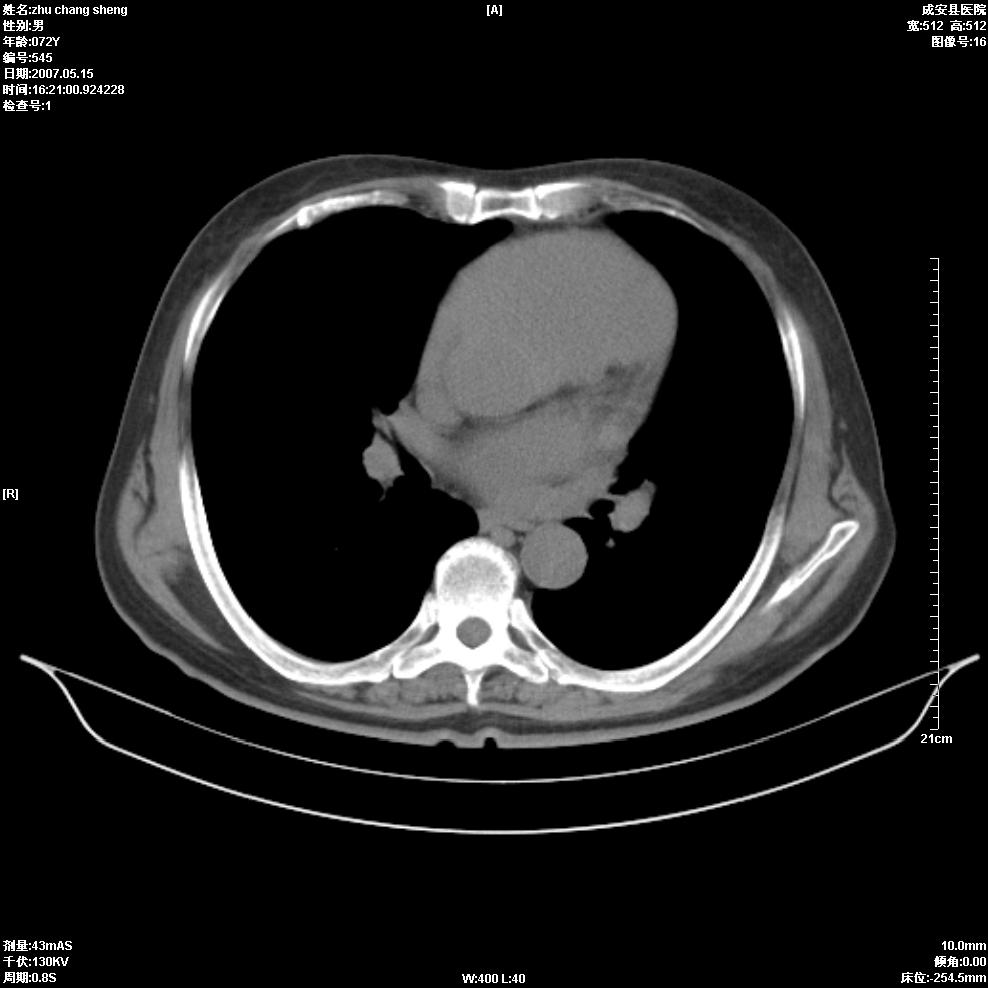

以下是引用医博云天在2007-5-15 19:10:00的发言:[br]心包积液,胸腔积液,心影增大,左心为主。

以下是引用zhangzhongshou在2007-5-15 20:21:00的发言:[br]心包积液可以肯定有,肿块显示不清,建议增强或mri检查。

以下是引用jinning在2007-5-15 21:06:00的发言:[br]心包积液可以肯定,建议增强或mri检查吧!

以下是引用拾荒者在2007-5-15 22:28:00的发言:[br]心包膜增厚,有少量积液,右室前壁示均匀软组织密度影,边界欠清,建议增强扫描或mri检查与室壁瘤鉴别。

以下是引用还珠格格在2007-5-19 9:50:00的发言:[br]病人与5月18日 做了核磁增强扫描 确诊为前上纵隔侵袭性胸腺瘤。